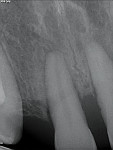

Opening space orthodontically may result in crown tipping, which can leave the roots of adjacent teeth converging into the prospective implant site. When this occurs, the resultant clinical inter-crown space may be deceptive and not indicative of pure bodily movement. If the mechanics for translation are correct, the crown and the root move together, and the correct pathway for implant placement is assured.8 When possible, overcorrection of the root angulations by tipping the roots more divergently than necessary allows for an easier and safer implant placement. Once the implant is placed and integrated, the adjacent roots can be moved back into proper alignment.

Orthodontic Phase

Tipping proved difficult to control; therefore, during the course of treatment, adjustments in mechanics were needed to ensure proper root alignment (Figure 28).To counteract the tipping movements associated with space closure via chain or open coil, the brackets were purposely misaligned. Because space opening can be deceptive, root angulation and bodily movement must be confirmed (Figure 29 through Figure 33). After 18 months, the upper and lower teeth were aligned, the occlusion was improved, and the case was set up for implant placement.